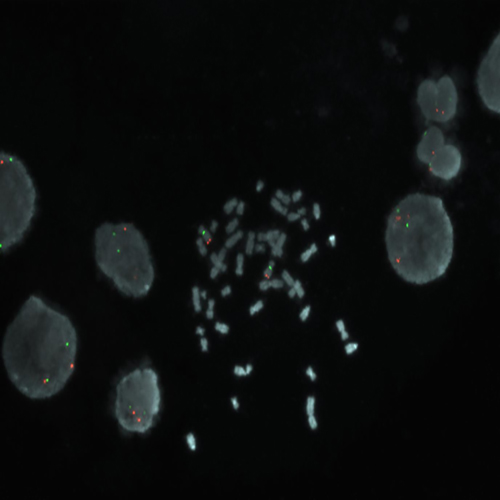

RUO - MYC (8q24) / SE 8 (D8Z1)

The MYC (previously known as C-MYC) gene produces an oncogenic transcription factor that affects diverse cellular processes involved in cell growth, cell proliferation, apoptosis and cellular metabolism. The MYC oncogene has been shown to be amplified in many types of human cancer such as bladder, breast and cervical. Amplification at 8q24 including MYC is also observed in 5% of CLL patients. MYC is also the prototype for oncogene activation by chromosomal translocation. The MYC (8q24) specific FISH probe is optimized to detect copy numbers of the MYC gene region at 8q24. The chromosome 8 Satellite Enumeration FISH probe (SE 8) at D8Z1 is included to facilitate chromosome identification.